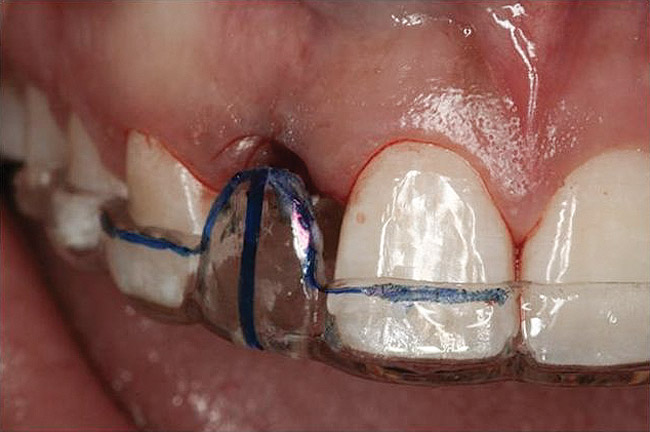

Figure 10 Clinical examination of the bound edentulous space: Measurement of the distal (Fig 10) and mesial (Fig 11) interproximal tissue height using a periodontal probe supplements data obtained from the periapical radiograph. Estimation of the buccal t

Figure 10

Figure 11 Clinical examination of the bound edentulous space: Measurement of the distal (Fig 10) and mesial (Fig 11) interproximal tissue height using a periodontal probe supplements data obtained from the periapical radiograph. Estimation of the buccal t

Figure 11

Figure 12 Clinical examination of the bound edentulous space: Measurement of the distal (Fig 10) and mesial (Fig 11) interproximal tissue height using a periodontal probe supplements data obtained from the periapical radiograph. Estimation of the buccal t

Figure 12